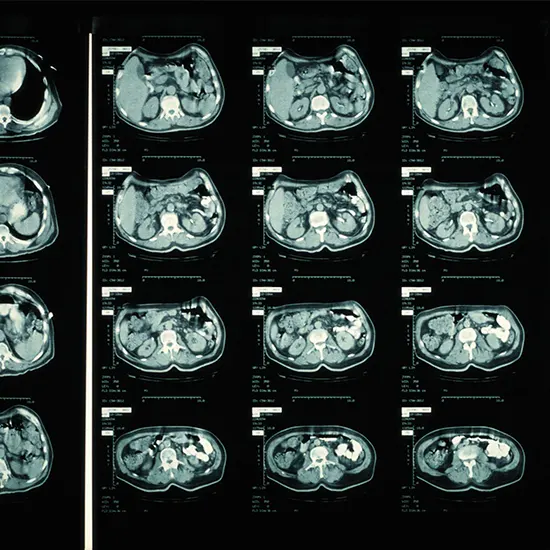

Computed Tomography or a CT filter may be a demonstrative imaging strategy where X-rays are utilized to envision the interior of your body.

Computed Tomography or a CT filter may be a demonstrative imaging strategy where X-rays are utilized to envision the interior of your body. The pictures captured by the X-rays are sent to a computer with fitting program innovation that makes a different change over the pictures captured into a discernable two-dimensional arrangement.

A CT scan is utilized to see bones, muscles, joints(knee, bear, etc.), inner organs just like the heart, midriff, and insides, fat tissue, and blood vessels. It gives a more point by point see of the human body parts than a standard X-ray and Ultrasound imaging.

In conclusion, Computed Tomography or a CT check could be a symptomatic imaging procedure that employs X-rays to envision the inner body structures which are at that point changed over into readable formats using computer computer program innovation. A differentiated CT consists of infusing a contrast dye into the body which makes a difference between distinctive tissues within the body.

The pictures are examined and detailed for ordinary and anomalous discoveries by a radiologist. A CT scan is utilized within the determination of wounds, inner organ pathology and cancers and to screen the movement of an illness and the effectiveness of treatment.